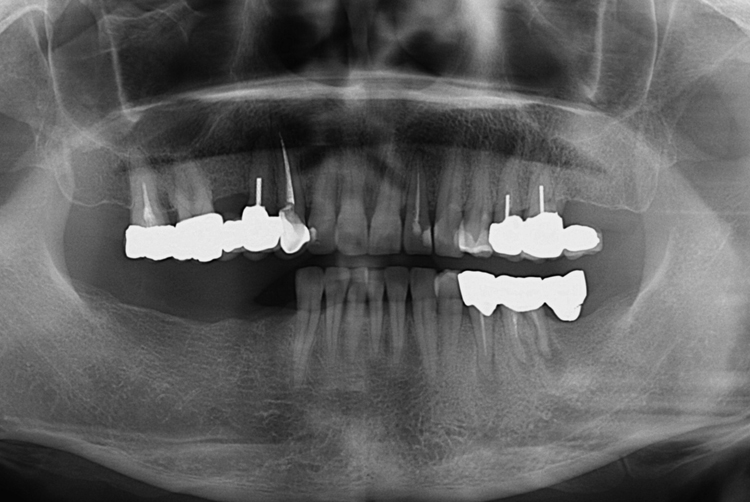

[임플란트] 어금니 임플란트

치료전 : 2018-09-20